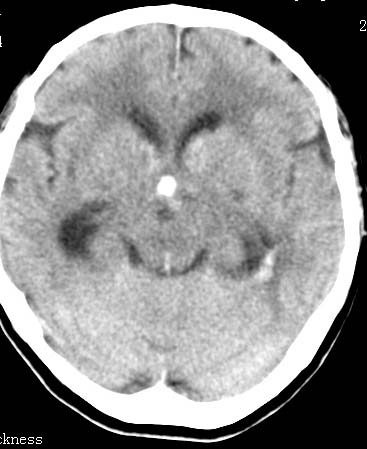

男性 病人 请大家看看出血的部位究竟在哪里?

是不是脑室系统出血啊! 伴轻度脑积水! 请老师指教!!

原发性脑室出血!

脑室系统出血,并脑积水.

我觉得是左侧侧脑室体旁出血,破入脑室系统.理由:除了左侧脑室体部外缘不规则之外,还有就是左侧脑室里面出血量较右侧多!

应该是左侧侧脑室内的出血导致其他脑室内的积血。

应该是尾状核出血破入侧脑室.

1、原发脑室出血,出血部位应该是左侧侧脑室;

2、左侧基底节区腔隙性脑梗塞;

(不考虑脑积水,脑室急性出血期脑室系统会轻度扩张)

脑室系统出血,第三脑室,侧脑室都有

出血点在左侧脑室旁。

左侧尾状核体部出血破入脑室系统.

最重要的是要讲明以脑室内积血为主,脑积水